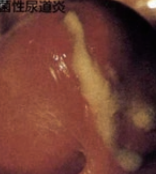

男性の尿道や性器にあらわれる淋病(淋菌)の写真・画像

淋病(淋菌)感染に特徴的なドロドロした乳白色の膿が尿道から出ている

少し乳白色の膿が出てくる

(写真参照)